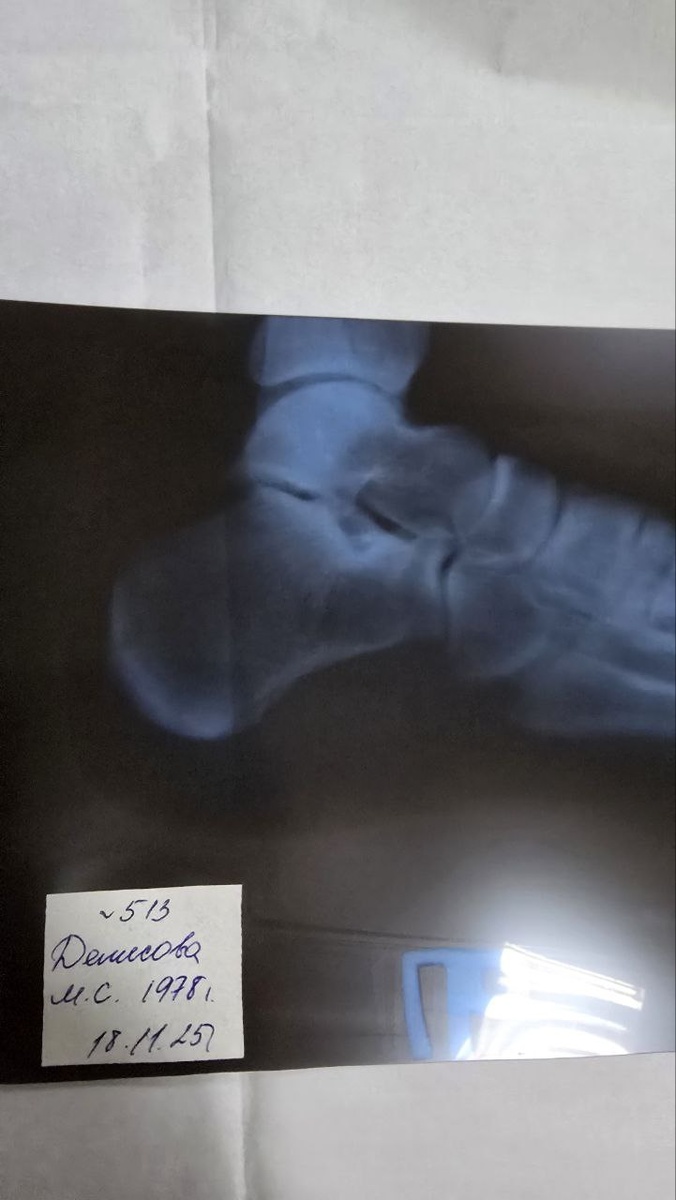

Мой снимок

Мой снимок😊